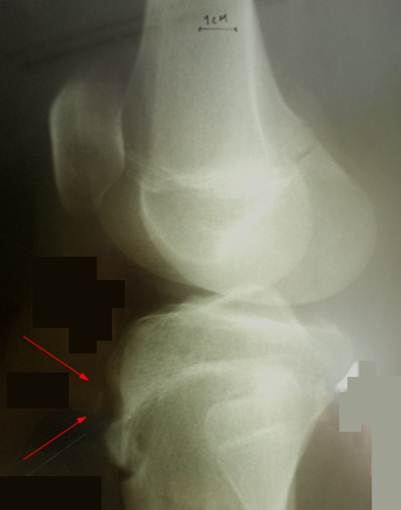

Боковой

снимок коленного сустава мальчика 14 лет.

Жалобы на плотное, безболезненное образование в области бугристости

большеберцовой кости. В анамнезе 1 год назад

имелась болезнь Огуста – Шлаттера

с типичными проявлениями ( боль, отек). Симптомы прошли в течение 2

месяцев. На момент осмотра жалоб на боль нет. В области бугристости

определяется твердое, округлое, неподвижное образование размером с лесной орех.

На снимке образование рентгенонегативное,

вдается в ткань эпифиза (обозначено стрелками). Такое явление иногда имеет место: после болезни Огуста – Шлаттера

в толще бугристости могут образовываться плотные фиброзные узлы. Рекомендовано удаление новообразования. При

операции обнаружен плотный узел из слабо

васкуляризованной ткани, напоминающей хрящ. Удален в пределах неизмененных

тканей. Гистологическое заключение:

костно – хрящевая дисплазия.